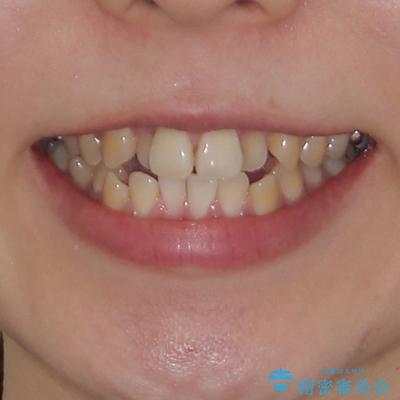

- 前歯のデコボコを気にして来院された患者様です。

前歯のデコボコはもちろん気になるところですが、舌の突出癖により上下前歯が非接触となっている状態でした。

上下前歯が非接触である開咬は、インビザラインによる治療がお勧めではありますが、しっかりと使う自信がないとのことで、ワイヤー装置にて治療を行うこととしました。

デコボコはあっという間に改善されましたが、開咬の改善に時間がかかりました。

舌の突出癖改善のトレーニングをしっかりと行っていただき、上下前歯が接触する咬み合わせを達成することができました。